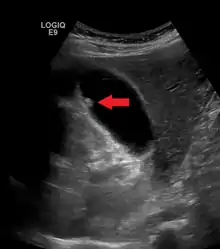

Adenomyomatosis describes a diseased state of the gallbladder in which the gallbladder wall is excessively thick, due to proliferation of subsurface cellular layer. It is characterized by deep folds into the muscularis propria. Ultrasonography may reveal the thickened gallbladder wall with intramural diverticulae, called Rokitansky-Aschoff sinuses.[3]

Diagnosis is typically by ultrasound or CT imaging.

Ultrasound image of gallbladder polyps measuring 3–7 mm.